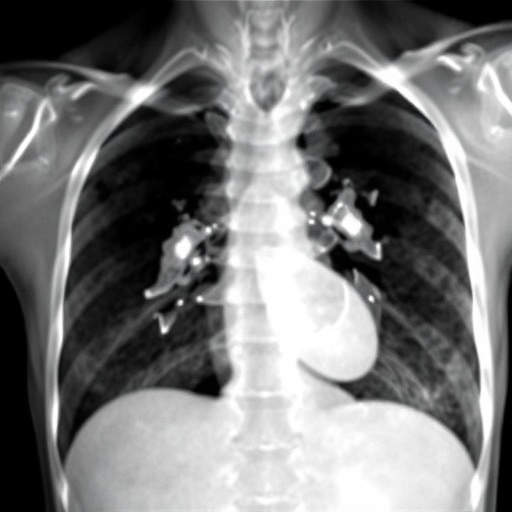

The case report highlights a patient diagnosed with Glanzmann Thrombasthenia who developed pulmonary thromboembolism, a potentially life-threatening condition. The detailed clinical presentation of this patient underscores the multifaceted nature of managing Glanzmann Thrombasthenia, which typically focuses on bleeding management rather than thrombotic events. The case serves as an urgent reminder of the need to reevaluate treatment plans that may overlook thrombotic risks in such patients.

Subject of Research: Pulmonary thromboembolism in Glanzmann Thrombasthenia

Article Title: Pulmonary thromboembolism in Glanzmann Thrombasthenia: a case report and systematic literature review